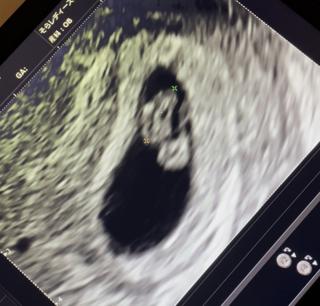

心音確認出来ました(*^^*)

心拍125

CRL6.2

心拍確認とれました(^^)

どうか無事に出産できますように。 神様お願いします!